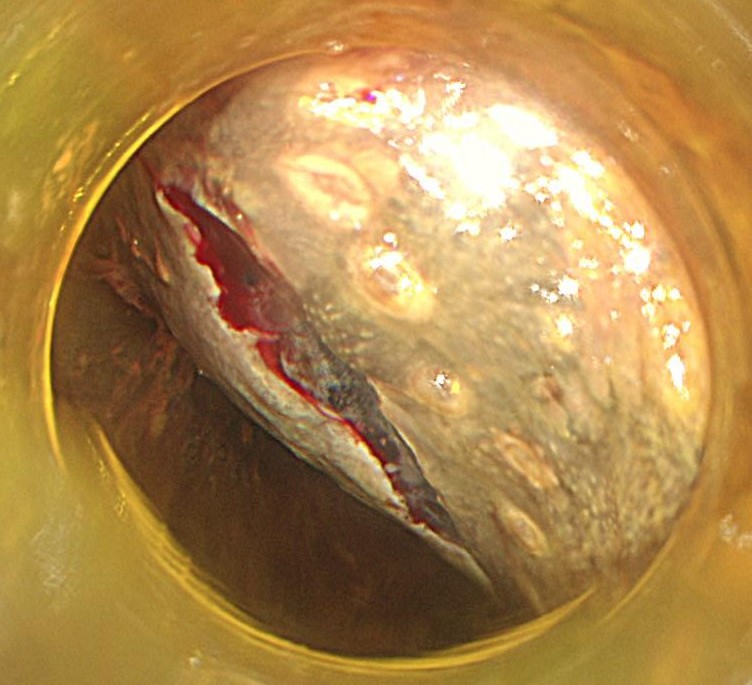

切除終了後の粘膜欠損部です。この後、1か月しっかりと胃薬を飲んでもらいます。

切除後標本です。しっかりと病変が切除できています。病理学的にも根治切除と診断されました。